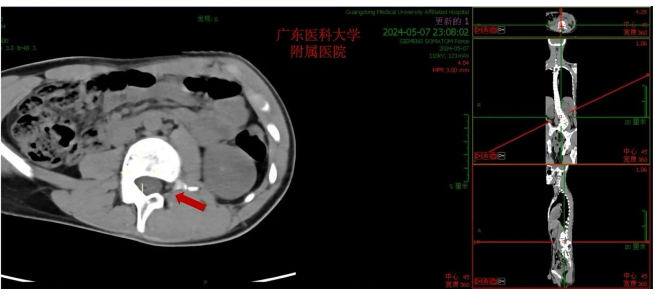

该青少年患者,腰骶段半椎体畸形,先天性脊柱侧凸,腰弯(L3-L5)Cobb角73.40°,脊柱侧凸角度大,为重度先天性脊柱侧凸,同时患者L2左侧椎弓根缺如,脊柱侧凸矫形手术难度大。根据患者具体情况,科主任魏波教授组织全科讨论评估患者病情,做了详细的术前评估,并制定了完善的手术方案及策略。

在胡资兵主任医师的指导下,由郑锦畅副主任医师及林瀚主治医生给患者行了经后路腰骶段半椎体切除、L1- L5椎弓根螺钉联合S2骶髂关节螺钉内固定、脊柱侧凸矫形、后外侧植骨融合术,手术过程顺利,术后患者康复迅速,取得满意的矫形效果,让患者挺起脊梁。